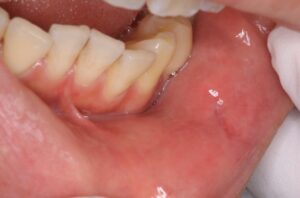

唇の粘膜の下に、半透明で丸くぷくっとした腫れができることがあります。

術前

これは、唇を噛むなどの刺激で唾液の通り道が傷つき、出口を失った唾液が周囲の組織の中に漏れて風船状に溜まってしまうことで生じます。

見た目は少し青みがかって見えることもありますが、細胞が増殖した癌(悪性腫瘍)とは性質が全く異なる、液体が溜まった良性の袋です。